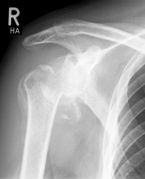

left: X-ray image of an omarthrosis

right: X-ray of a healthy shoulder joint

X-rays can be used to reliably diagnose the extent of joint wear. In the case of severe osteoarthritis, for example, the joint space and the formation of jagged edges (osteophytes) can be detected. If additional damage to the tendons of the shoulder (rotator cuff) is suspected, ultrasound examination (sonography) or magnetic resonance imaging (MRI) can help clarify the situation.